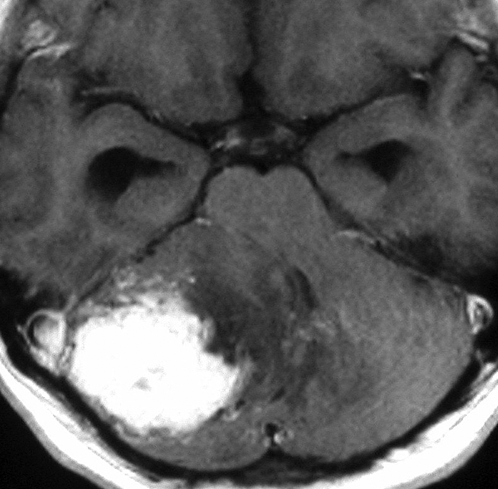

フォンヒッペルリンドウ病に合併した大きな右小脳半球血管芽腫です。大きなものでは静脈環流障害(鬱滞)のために脳浮腫を来すことが多いし,その分,手術時の静脈圧が高くて止血が難しいと考えなければなりません。水頭症を呈して症状は重篤でしたが,右後頭窩開頭で比較的簡単に全摘出できて回復しました。小脳半球に生じるものは手術で大きな障害を残すことはほとんどなく術後の症状症状の回復も順調なことが多いです。

同じ患者さんです。上記の手術の5年後に新たな血管芽腫が激しく増大しました。これは小脳虫部なので両側の上小脳動脈がfeeding arteryとなります。bilateral occipital transtentorial approachという特殊な手術方法でしか摘出できません。幸いこの腫瘍も無事に全摘出できました。